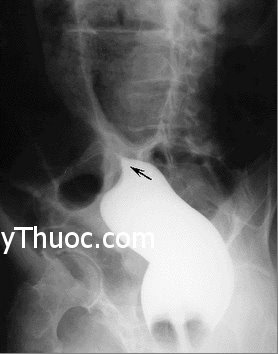

Hình ảnh xoắn đại tràng trên phim Xquang.

Chụp phim Xquang có thể chẩn đoán xác định 60-70% các trường hợp xoắn đại tràng xích-ma với hình ảnh ống hơi hình chữ U lộn ngược chiếm gần hết ổ bụng, hai chân của chữ U hướng về vùng hốc chậu; đại tràng phải giãn và chứa đầy phân; đại tràng xuống bị kéo về đường giữa… Chụp Xquang bụng có thể chẩn đoán xác định hầu hết các trường hợp xoắn manh tràng, với hình ảnh: một “khối hơi” có các đặc điểm của manh tràng. Chụp Xquang đại tràng với Barium vừa có tác dụng chẩn đoán vừa có tác dụng điều trị.